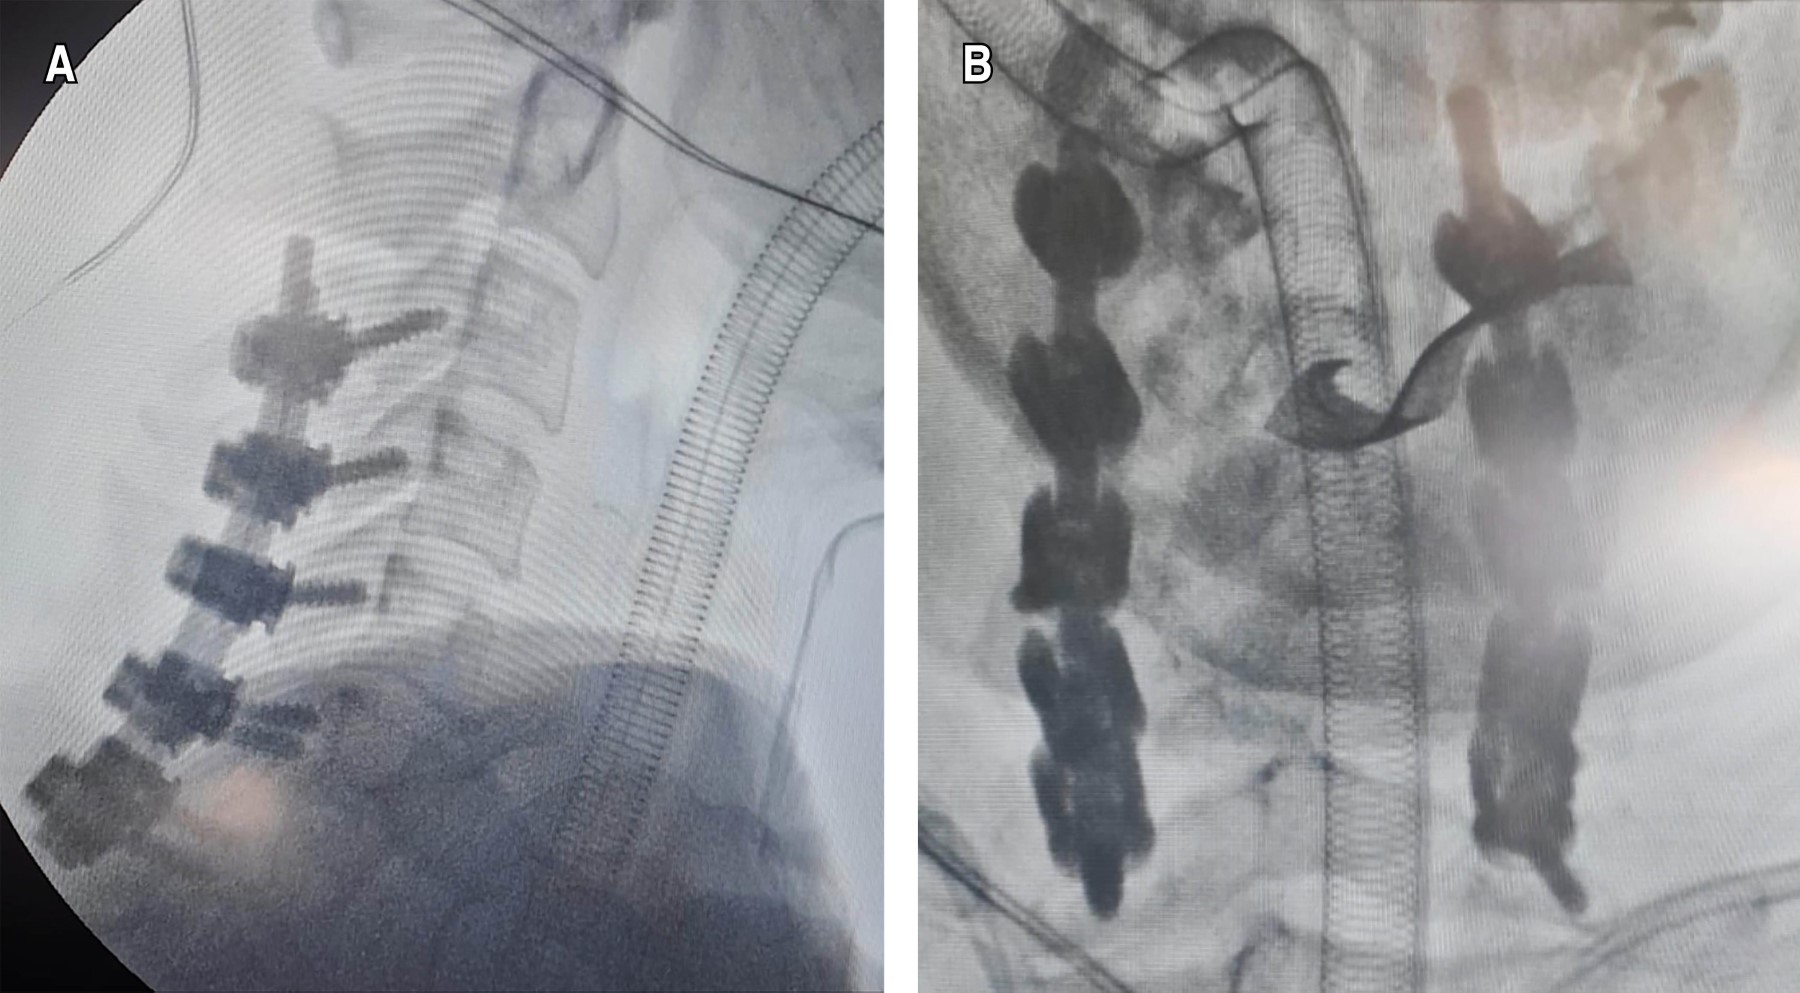

Ewing sarcoma (ES) is a malignant tumor that generally occurs in pediatric males. Its location in the neck is rare, with extraosseous presentation in this area being exceptional (3.4%), even more if it is extramedullary intradural. The presence of non-specific clinical symptoms makes early detection difficult, which tends to occur when the tumor causes spinal cord involvement, requiring an urgent surgical approach. We present the case of a 49-year-old female patient with neck pain of two years' duration, who after a symptomatic exacerbation lasting one month, presented right hemiparesis and loss of sphincter control. Diagnostic approach with magnetic resonance imaging showed multidirectional bulging of the annulus fibrosus measuring 300 × 300 × 100 mm, located at C3-T1 that compressed the dural sac plus bilateral neural foraminal involvement. Surgical management through a posterior cervical approach plus stabilization of lateral masses from C3 to C7, with a histopathological report of Ewing sarcoma complemented by detection of the t(11;22)(q24;q12) translocation of EWSR1. After surgery, the patient showed improvement with independence in work activity and daily life.

Figure 1